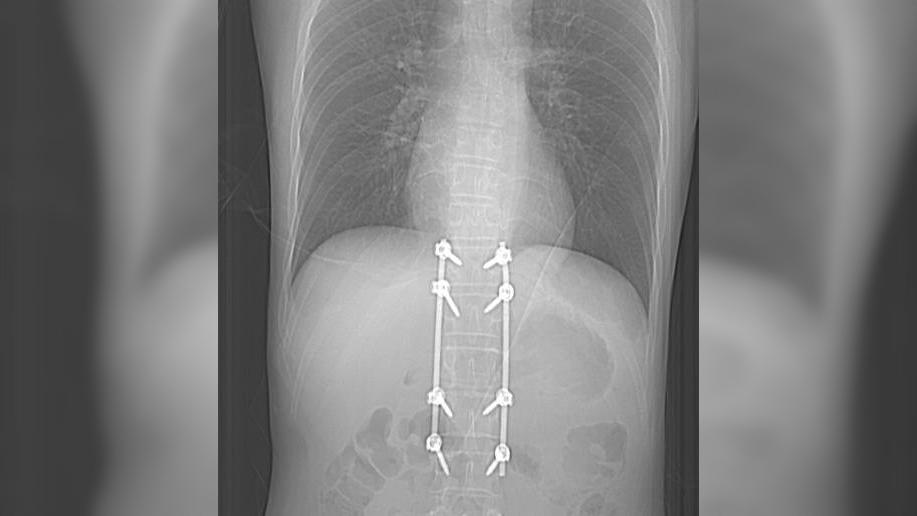

Медики также обнаружили и устранили у пациента повреждения желчевыводящих путей. Из-за этого пострадавшему удалили желчный пузырь и провели дренирование холедоха. Затем пострадавшему потребовалась операция на позвоночнике с транспедикулярной фиксацией.